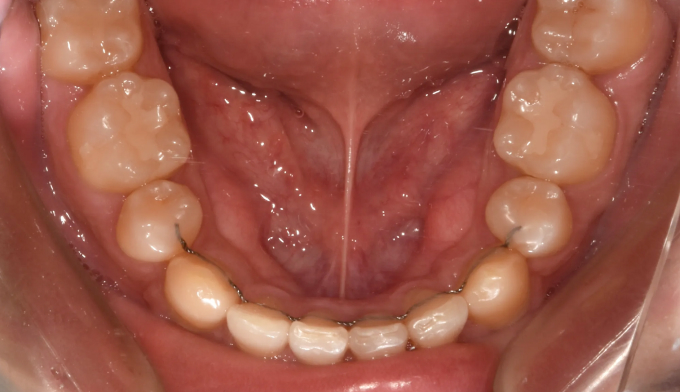

덧니

필요한 공간이 많지 않아도, 입이 많이 나오지 않아도 발치교정을 해야하는 경우들이 종종 있습니다.

비발치교정시 주로 악궁확장이나 치아삭제, 또는 치아 후방이동을 통해 공간을 확보하는데 기존의 악궁이 충분히 넓거나 치아크기가 작은경우, 또는 사랑니가 너무 깊숙히 있어서 발치하기 어려운 경우에는 어쩔 수 없이 작은어금니 발치를 통해 공간을 확보합니다.

교정기간은 총 22개월입니다.